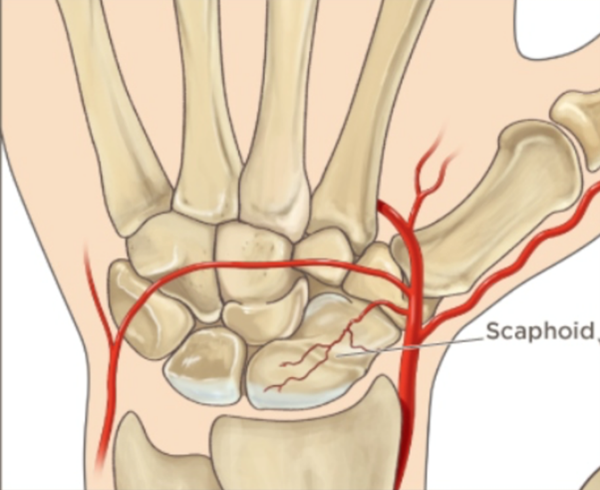

- 주상골은 손목 관절뼈 중 중요한 역할을 합니다. 그런데 골절이 된 이후에는 뼈가 잘 붙지않는 불유합이나, 뼈에 혈액순환이 잘 안되서 뼈가 녹아버리는 골괴사가 발생할 수 있습니다. 이렇게 쉽게 문제가 생기는 이유는 혈류가 적고, 골절 시 혈관손상으로 혈액공급에 문제가 쉽게 발생할 수 있기 때문입니다. 따라서 약간의 뼈의 어긋남이 있어도 뼈가 잘 붙지 않을 수 있습니다.

- 아래 그림에서 골괴사가 잘 되는 이유를 모식도로 잘 설명했습니다. 혈액이 한쪽에서면 공급이되기때문에 골절이 되면 골절된 끝부분의 혈액공급이 잘 안될 수 있기 때문입니다.